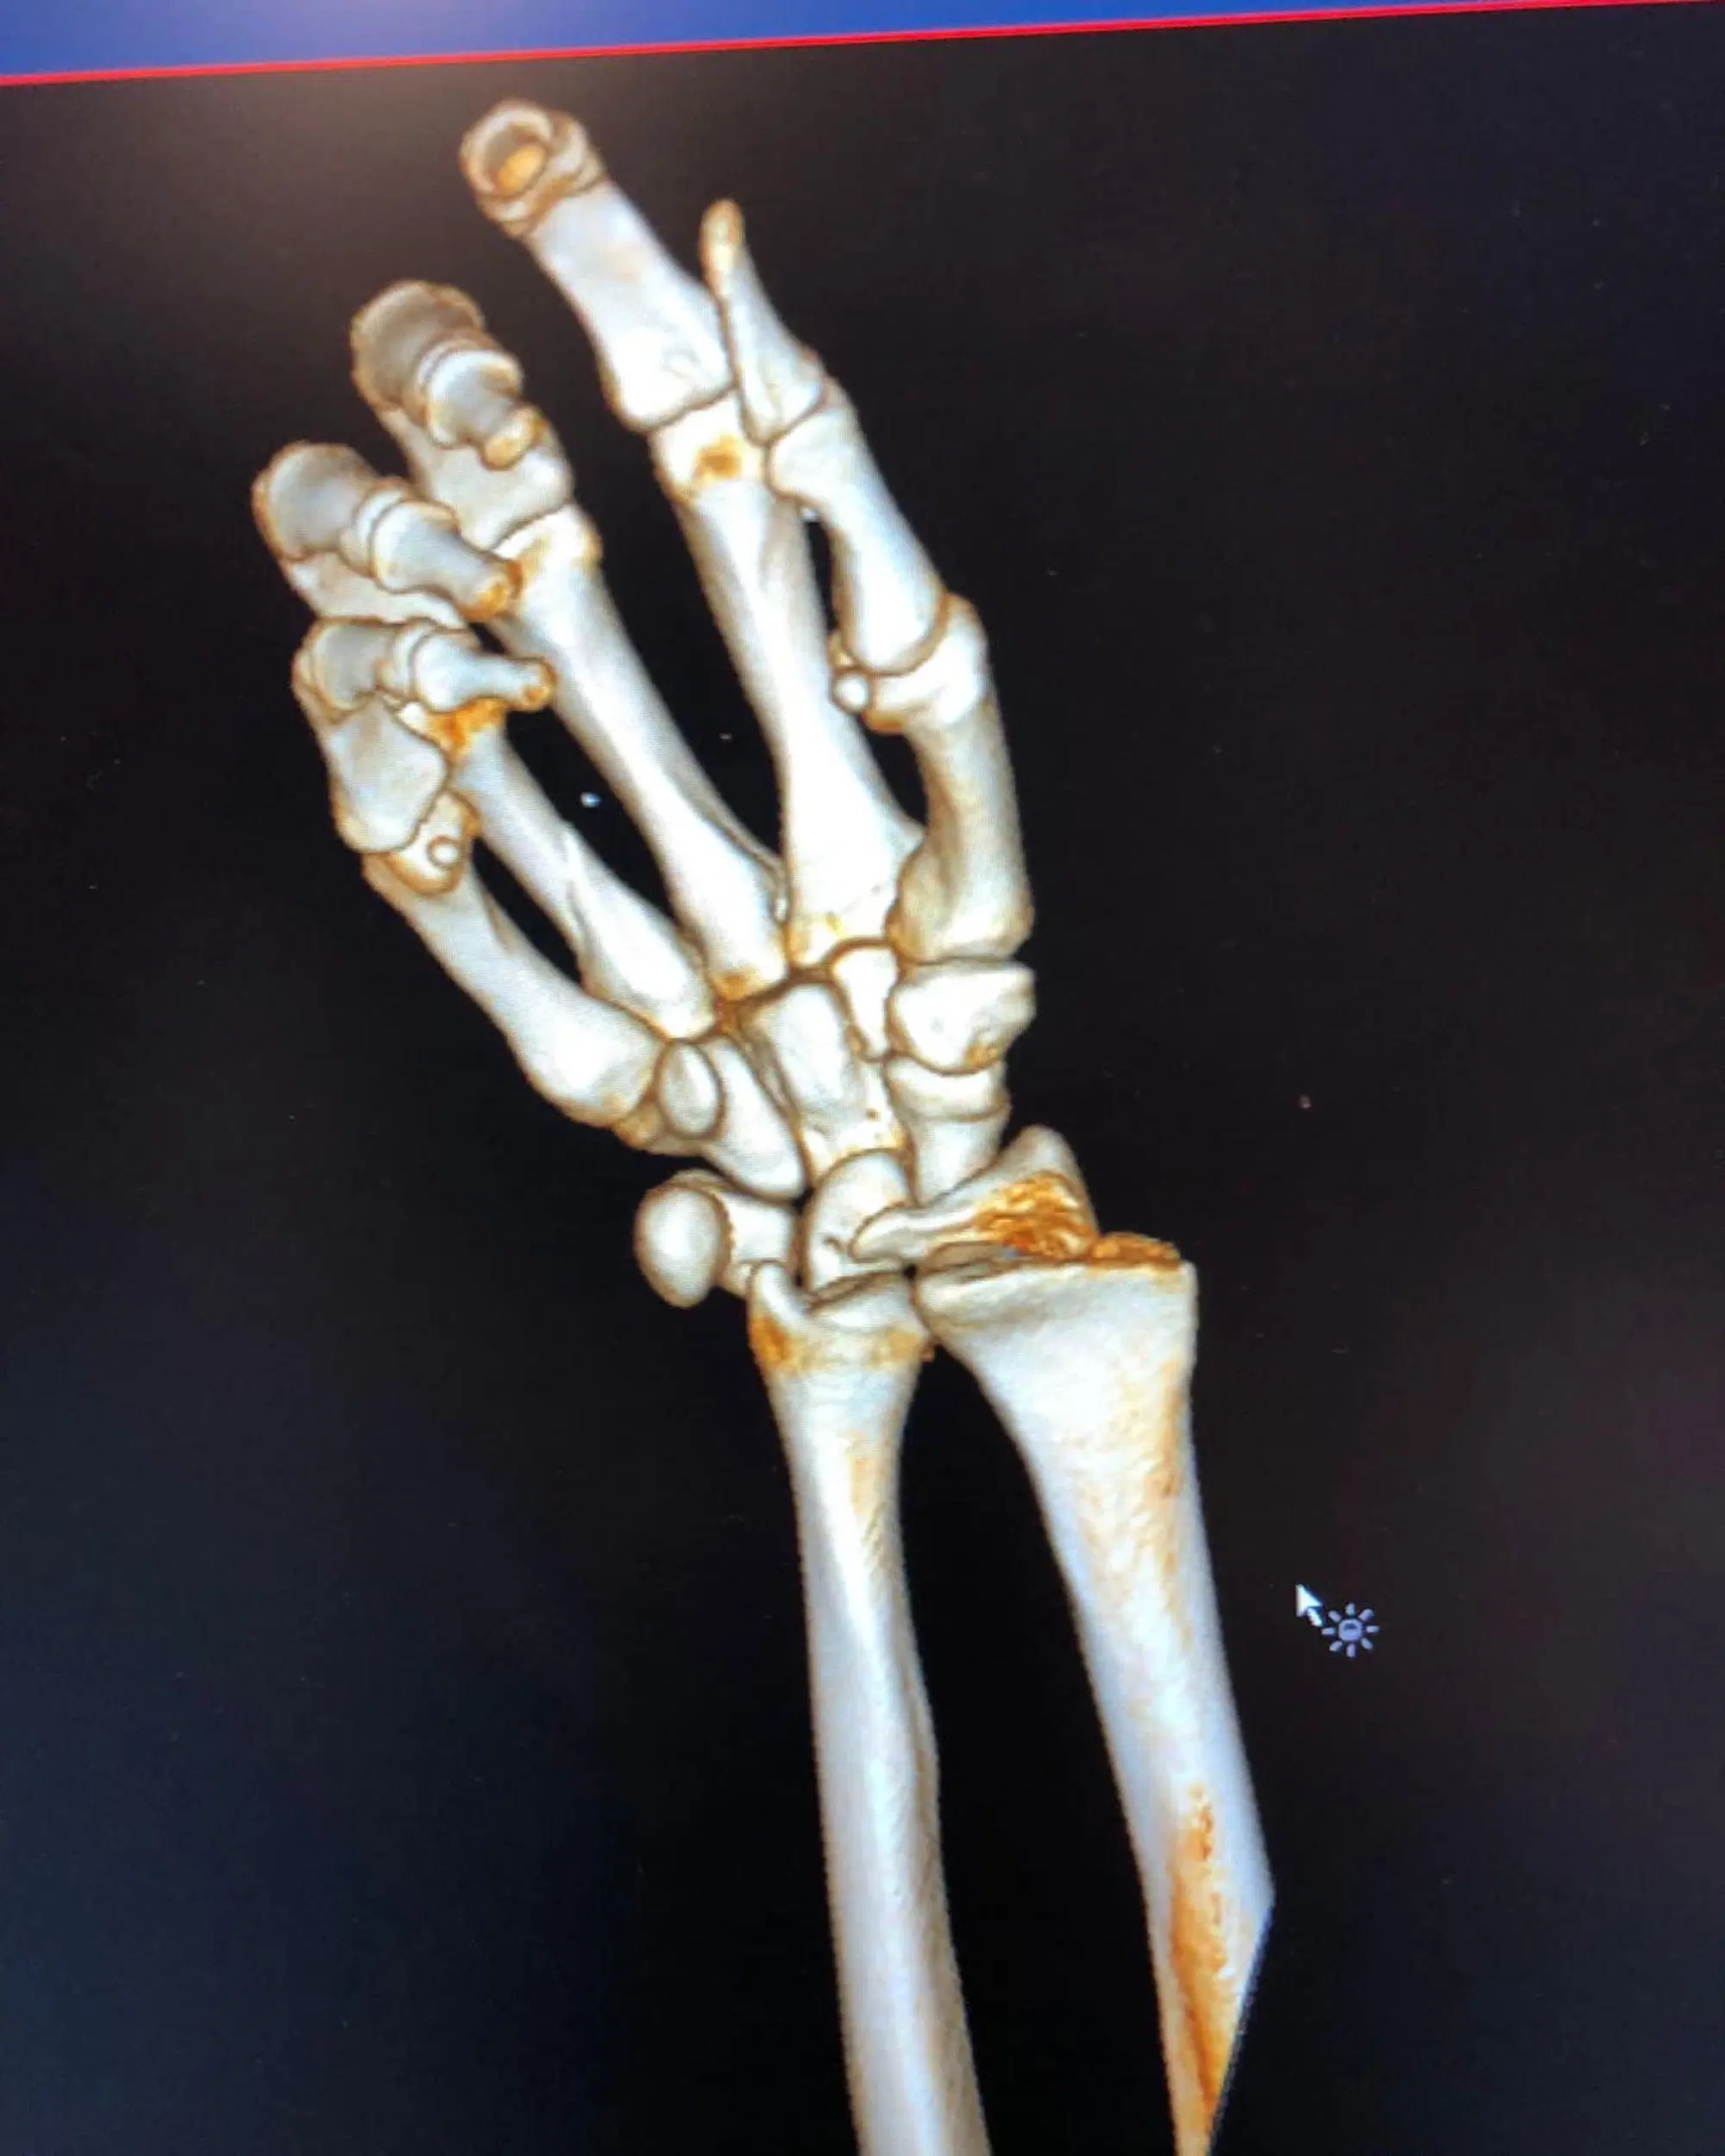

"C'è questa nuova moda che i crossisti seguono: far vedere le loro fratture - ha scritto il Dovi - E io, che un pò crossista mi sento non potevo non essere "in trend"...e ho deciso di giocarmi la carta della frattura del polso (scomposta per bene, naturalmente). Un paio d'ore di paura, ma fa parte del gioco. La cosa importante è che sto bene e non ho riportato danni permanenti.